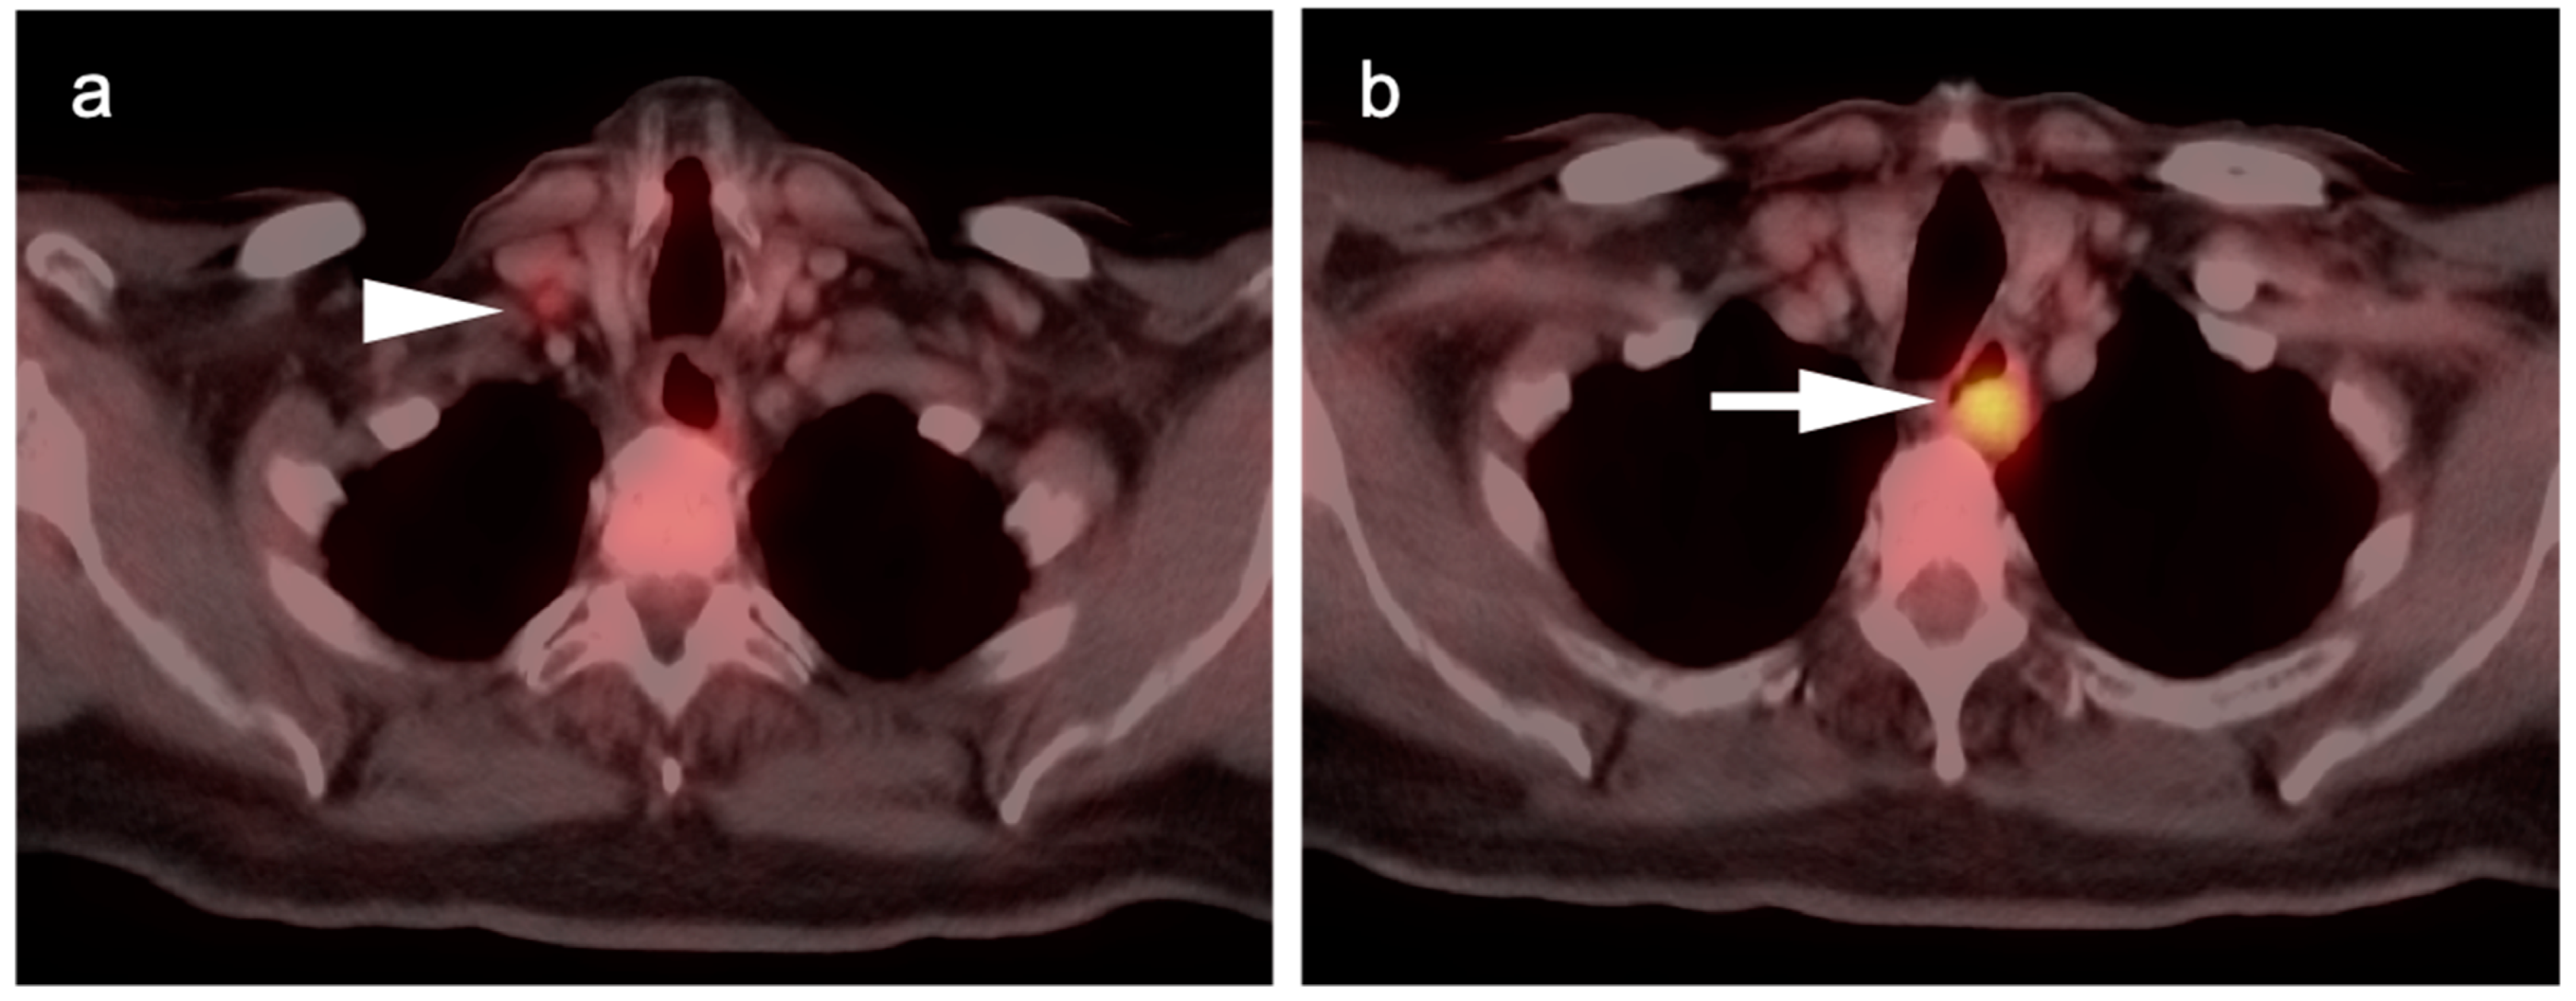

7. Adrenal Cancer